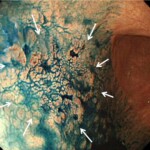

細胞の形が不揃いで、粘膜の下に潜り込むように広がることがあり、内視鏡では境界がはっきりしない場合があります。進行が早めの傾向があるため、胃がんの範囲や治療方法などは分化型胃がんより慎重な評価が必要です。

→未分化型胃がんの内視鏡画像。境界がはっきりせず、内視鏡治療は断念した症例

未分化型では、色や形の変化が乏しく境界が不明瞭なことがあり、より高度な拡大観察が必要です。

*潰瘍はないが2㎝以上ある未分化型胃がん ESDではなく外科的治療を受けて完治しました(矢印の範囲外にもがんが広がっています)